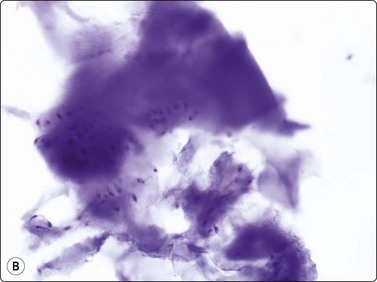

Chondroblastoma is a rare tumor, and most cases are found in children and adolescents. The cytology has been investigated in four series.21-25 Our experience is limited to a few cases. The double cell population and the fragments of chondroid material are the clues to the diagnosis. According to the series of 12 cases described by Fanning et al.,23 the cells resembling chondroblasts are typical. They are mononuclear and rounded with well-demarcated cytoplasm and rounded lobulated or reniform nuclei. Nuclei are centrally located, showing slight anisokaryosis. One feature often described is longitudinal grooves in nuclei. The chondroblast-like nuclei are either single or embedded in the chondroid fragments (Fig. 16.15).

image image

Fig. 16.15 Ewing’s sarcoma

(A) A mixture of cells with larger pale-staining nuclei and cells with smaller and darker nuclei; note the cytoplasmic vacuoles and clear spaces in the pale cells (MGG, HP oil); (B) Rosette-like structure; nuclear chromatin and nucleoli more clearly seen than in MGG (H&E, HP oil).